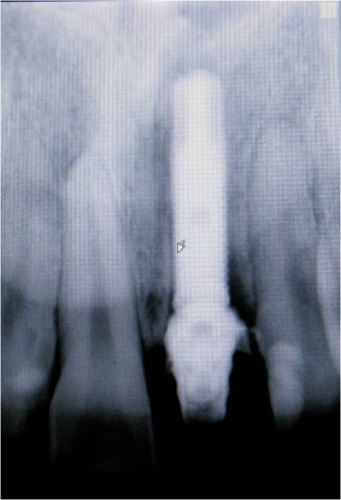

Caso 1 - Implante imediato após extração do dente fraturado (dente 11) e implante imediato

![]() |